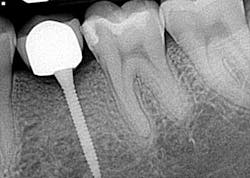

Hygiene. It can be agreed upon that if an implant can’t be kept clean, then the potential for failure and difficulties rise exponentially. A 90-degree angle between the implant and crown is virtually impossible to keep clean and maintain. As amazing as some hygienists are, it is impractical to expect that a curette can get into that space to clean it without making hamburger of the tissue. The implants were cemented on, so they are not easily retrievable. The emergence profile is nonexistent. Do natural teeth look like this? I would submit that when restoring implants, it is our job to mimic the shape and emergence profile of natural teeth as closely as possible. When we don’t, then we lose the inherent cooperation and benefits that the tissue can provide. To help the parents understand this concern, I showed them an example of a traditional implant vs. the “pumpkin on a toothpick” implant. The side-by-side comparison spoke for itself.

vs.

Longevity and function. Premolars don’t get the brunt of mastication forces, but they definitely get their fair share. If the occlusal forces are not centered over the implant just right, then we observe a first-class type of lever that can cause long-term stability issues. It could be argued by some that the 20 mm implant length could render a certain amount of support, but again, the aforementioned point must be referenced — there is/was adequate space for wider based platform implants to be placed.